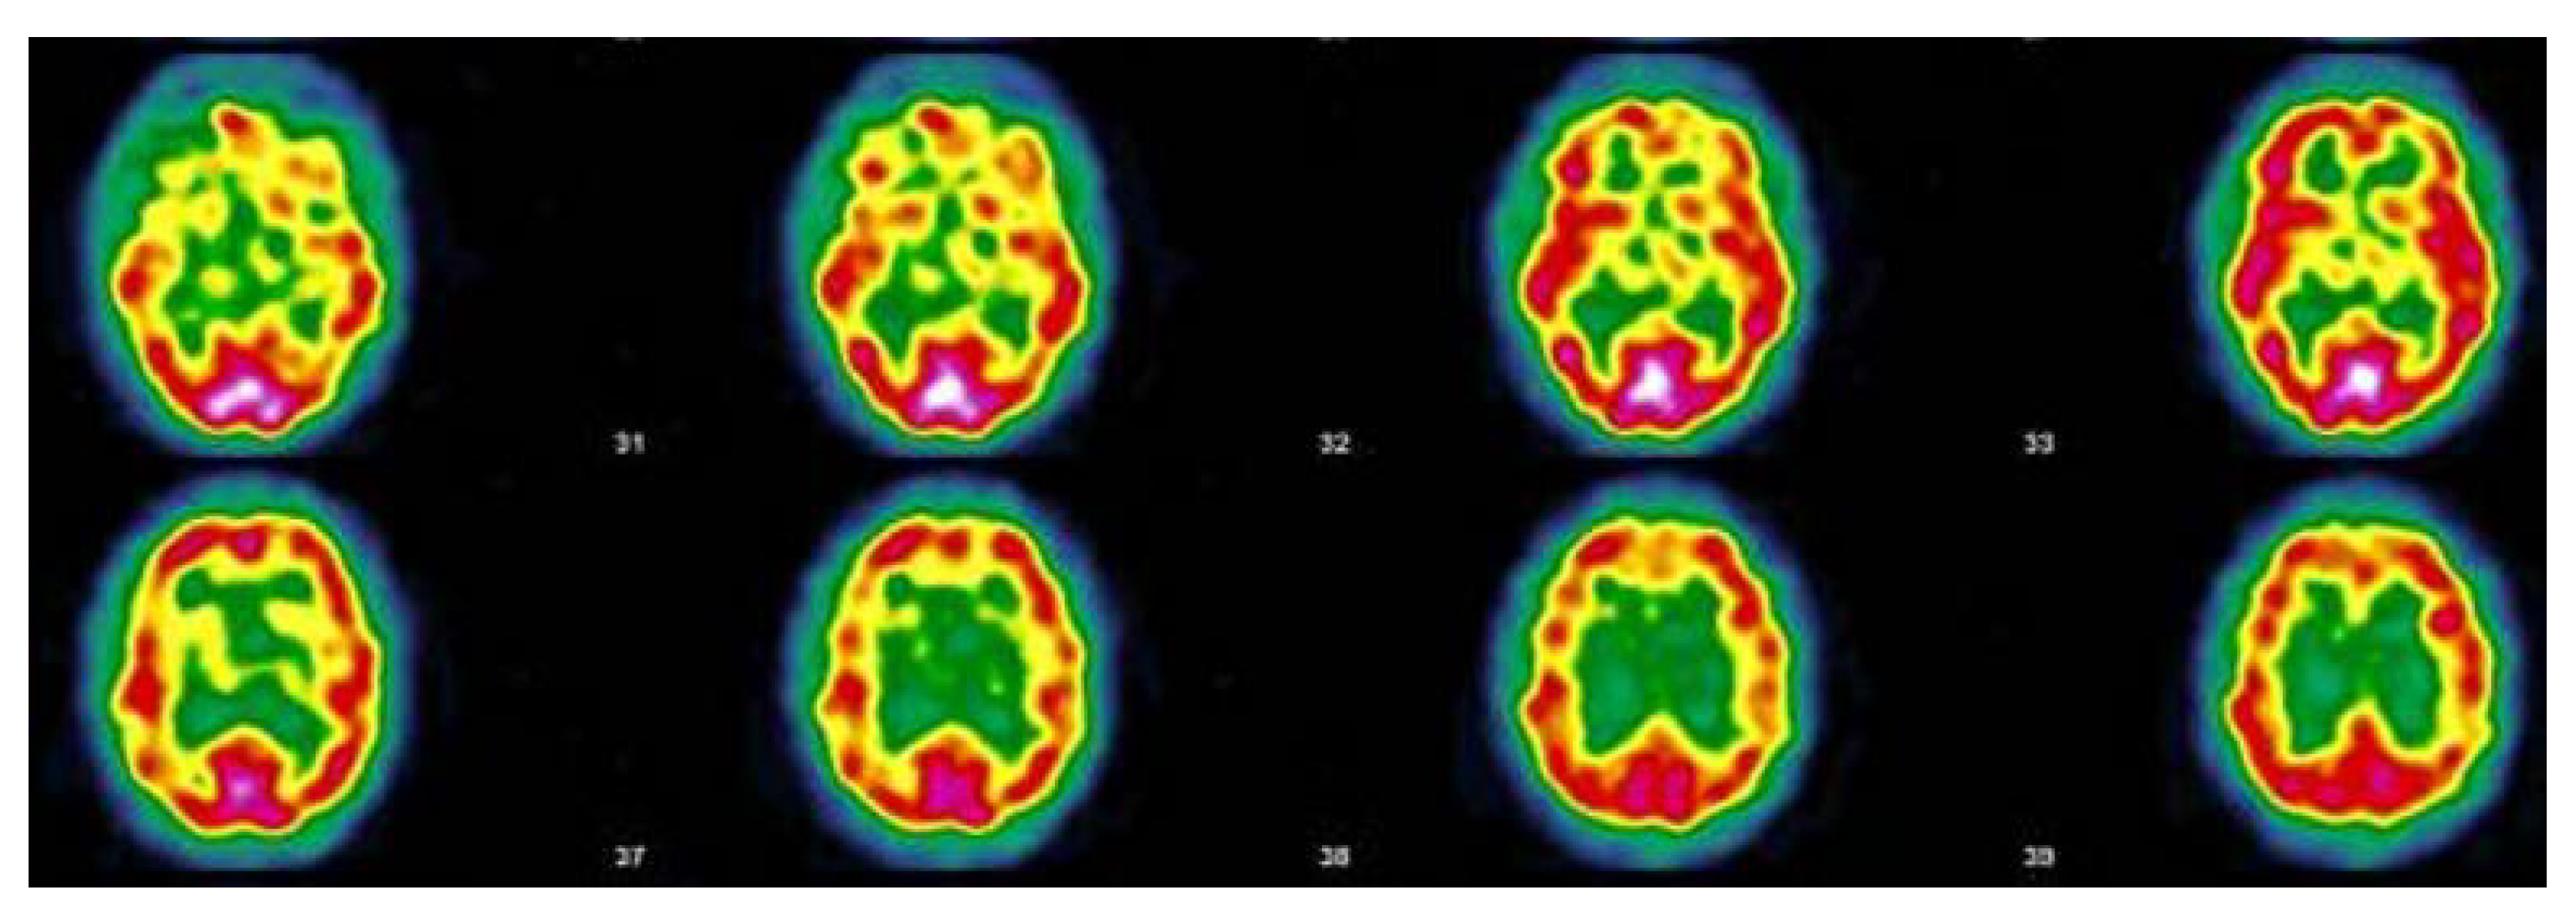

3.4. Nuclear Imaging Interest

- Cerebral hypo-perfusion demonstrated by SPECT-CT seems to correlate with the clinical symptoms in a cohort of PACS patients. This needs further studies.

| 13 October 2020 Throat pain, rhinorrhea, bad aches, severe fatigue and headache, but no breathing difficulties, dysgeusia, anosmia. Stays at home, cured after 12 days. Home care only | 11 November 2020 Pain in both eyes, ocular pruritus, rapid ocular fatigue, noise intolerance, memory loss (forgets to pick up her daughter at school), concentration problems, remains isolated in her room, dyspnea at the slightest effort and at speech, almost continuous osteoarticular and muscular pains often with headaches, abnormal dreams, depressive feeling, fatigue, post-exertional malaise (PEM) | 27 July 2021 “On the images taken, left fronto-parietal, left frontal and left thalamic hypofixation is observed. No preservation of the sensory motor cortices. The fixation in front of the cerebellum is correct. Conclusion: Scintigraphic examination compatible with a cerebral pathology of the vascular type with clearer left fronto-parietal, left frontal and left thalamic vascular disorders”. |

| 3 March 2021 Cough, aching, elevated temperature, headache, 20 days in bed, loss of taste, loss of smell, severe tinnitus, 20 days in total. Home care | 5 October 2021 Hearing loss in right ear, balance always disturbed, dizziness, loss of vision, quickly tired, severe weight gain, quickly out of breath, became depressed, pain in left hip every night, post-vaccinations headaches, memory loss, word retrieval deficit, repeats herself and doesn’t realize it, forgets which groceries she went to get, has trouble concentrating, disseminated myalgia, insomnia, loss of sense of direction | 17 November 2021 “Heterogeneous tracer distribution throughout the cortex, with more marked hypofixation in the bilateral predominantly left superior parietal, left parietal, bilateral medial temporal and bilateral predominantly right parieto-occipital areas. Diffuse subcortical periventricular hypofixation. The basal ganglia and cerebellum show preserved and symmetrical tracer uptake. Scintigraphic image suggestive of vascular damage in the broad sense.” |